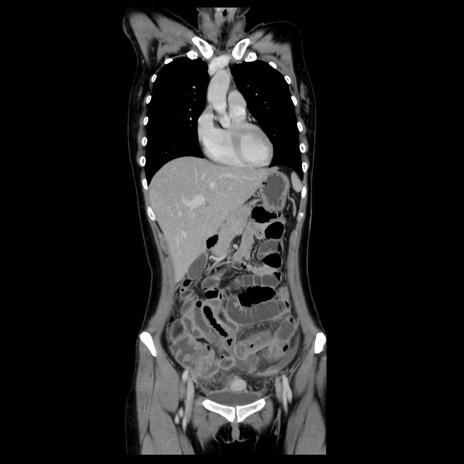

症例39(冠状断像)

CT